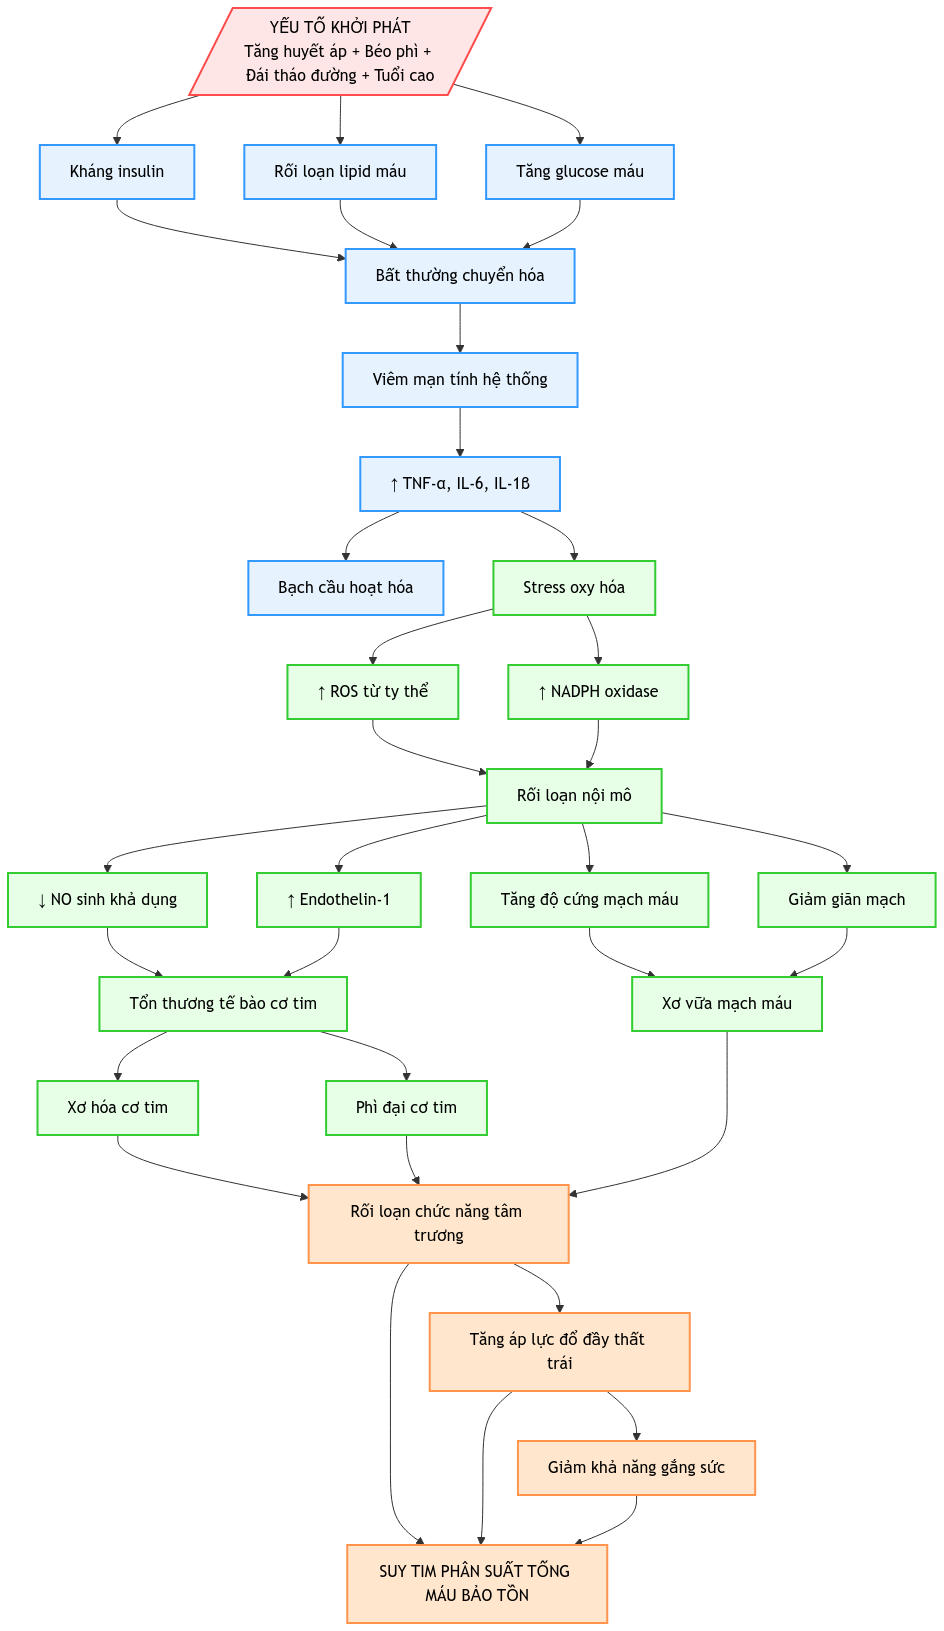

Phác đồ chẩn đoán và điều trị suy tim phân suất tống máu bảo tồn (HFpEF)

PHÁC ĐỒ CHẨN ĐOÁN VÀ ĐIỀU TRỊ SUY TIM PHÂN SUẤT TỐNG MÁU BẢO T [...]